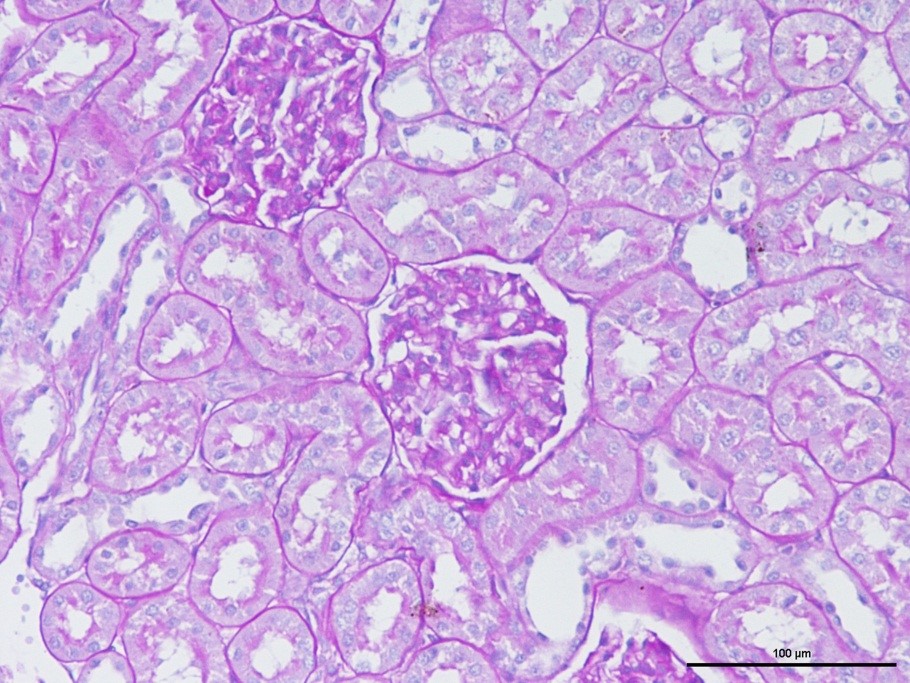

大鼠肾组织PAS染色效果

PAS染色利用高碘酸把糖类相邻两个碳上的羟基氧化成醛基,再用Schiff试剂和 醛基反应使呈现紫红色,显示糖原定位。

该染色方法可用于糖尿病肾病模型,用于显示肾小球病变中糖原沉积,基底膜增厚。